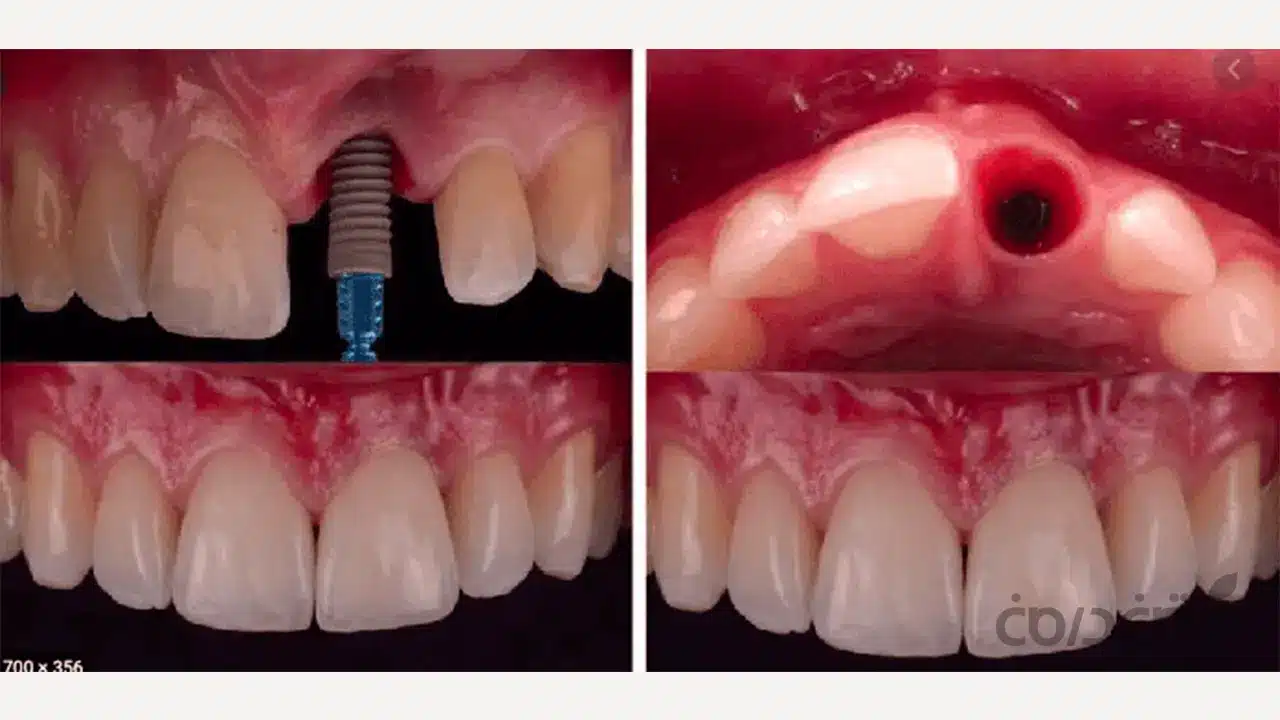

گام دوم: مدیریت حفره دندان؛ اولین قدم برای حفظ زیبایی

اگر دندان شما هنوز کشیدهنشده، نحوه خارج کردن آن نقش بسیار مهمی در آینده ایمپلنت دندان جلو شما دارد. ما این کار را “کشیدن آتروماتیک” می نامیم. یعنی دندان با ابزارهای بسیار ظریف و با کمترین آسیب ممکن به استخوان و لثه اطراف خارج می شود. حفظ آن دیواره نازک استخوانی در این مرحله، اولویت اصلی ما است.

در بسیاری از موارد، به خصوص اگر کاشت ایمپلنت به صورت فوری انجام نشود، ما از تکنیک حفظ حفره (Socket Preservation)استفاده می کنیم. در این روش، بلافاصله پس از کشیدن دندان، حفره خالی را با مواد پیوند استخوان پر می کنیم. این کار از تحلیل رفتن استخوان در ماه های آینده جلوگیری کرده و بستر را برای یک جراحی ایمپلنت موفق تر آماده می کند.

گام سوم: جراحی دقیق و مدیریت بافت ها

این مرحله از ایمپلنت دندان جلو، بخش اصلی درمان است. جراح (متخصص ایمپلنت) با استفاده از راهنما یا گاید جراحی که در مرحله برنامه ریزی دیجیتال ساختهشده، ایمپلنت را دقیقاً در همان موقعیت سه بعدی ایده آل در استخوان فک قرار می دهد. اما کار به اینجا ختم نمی شود.